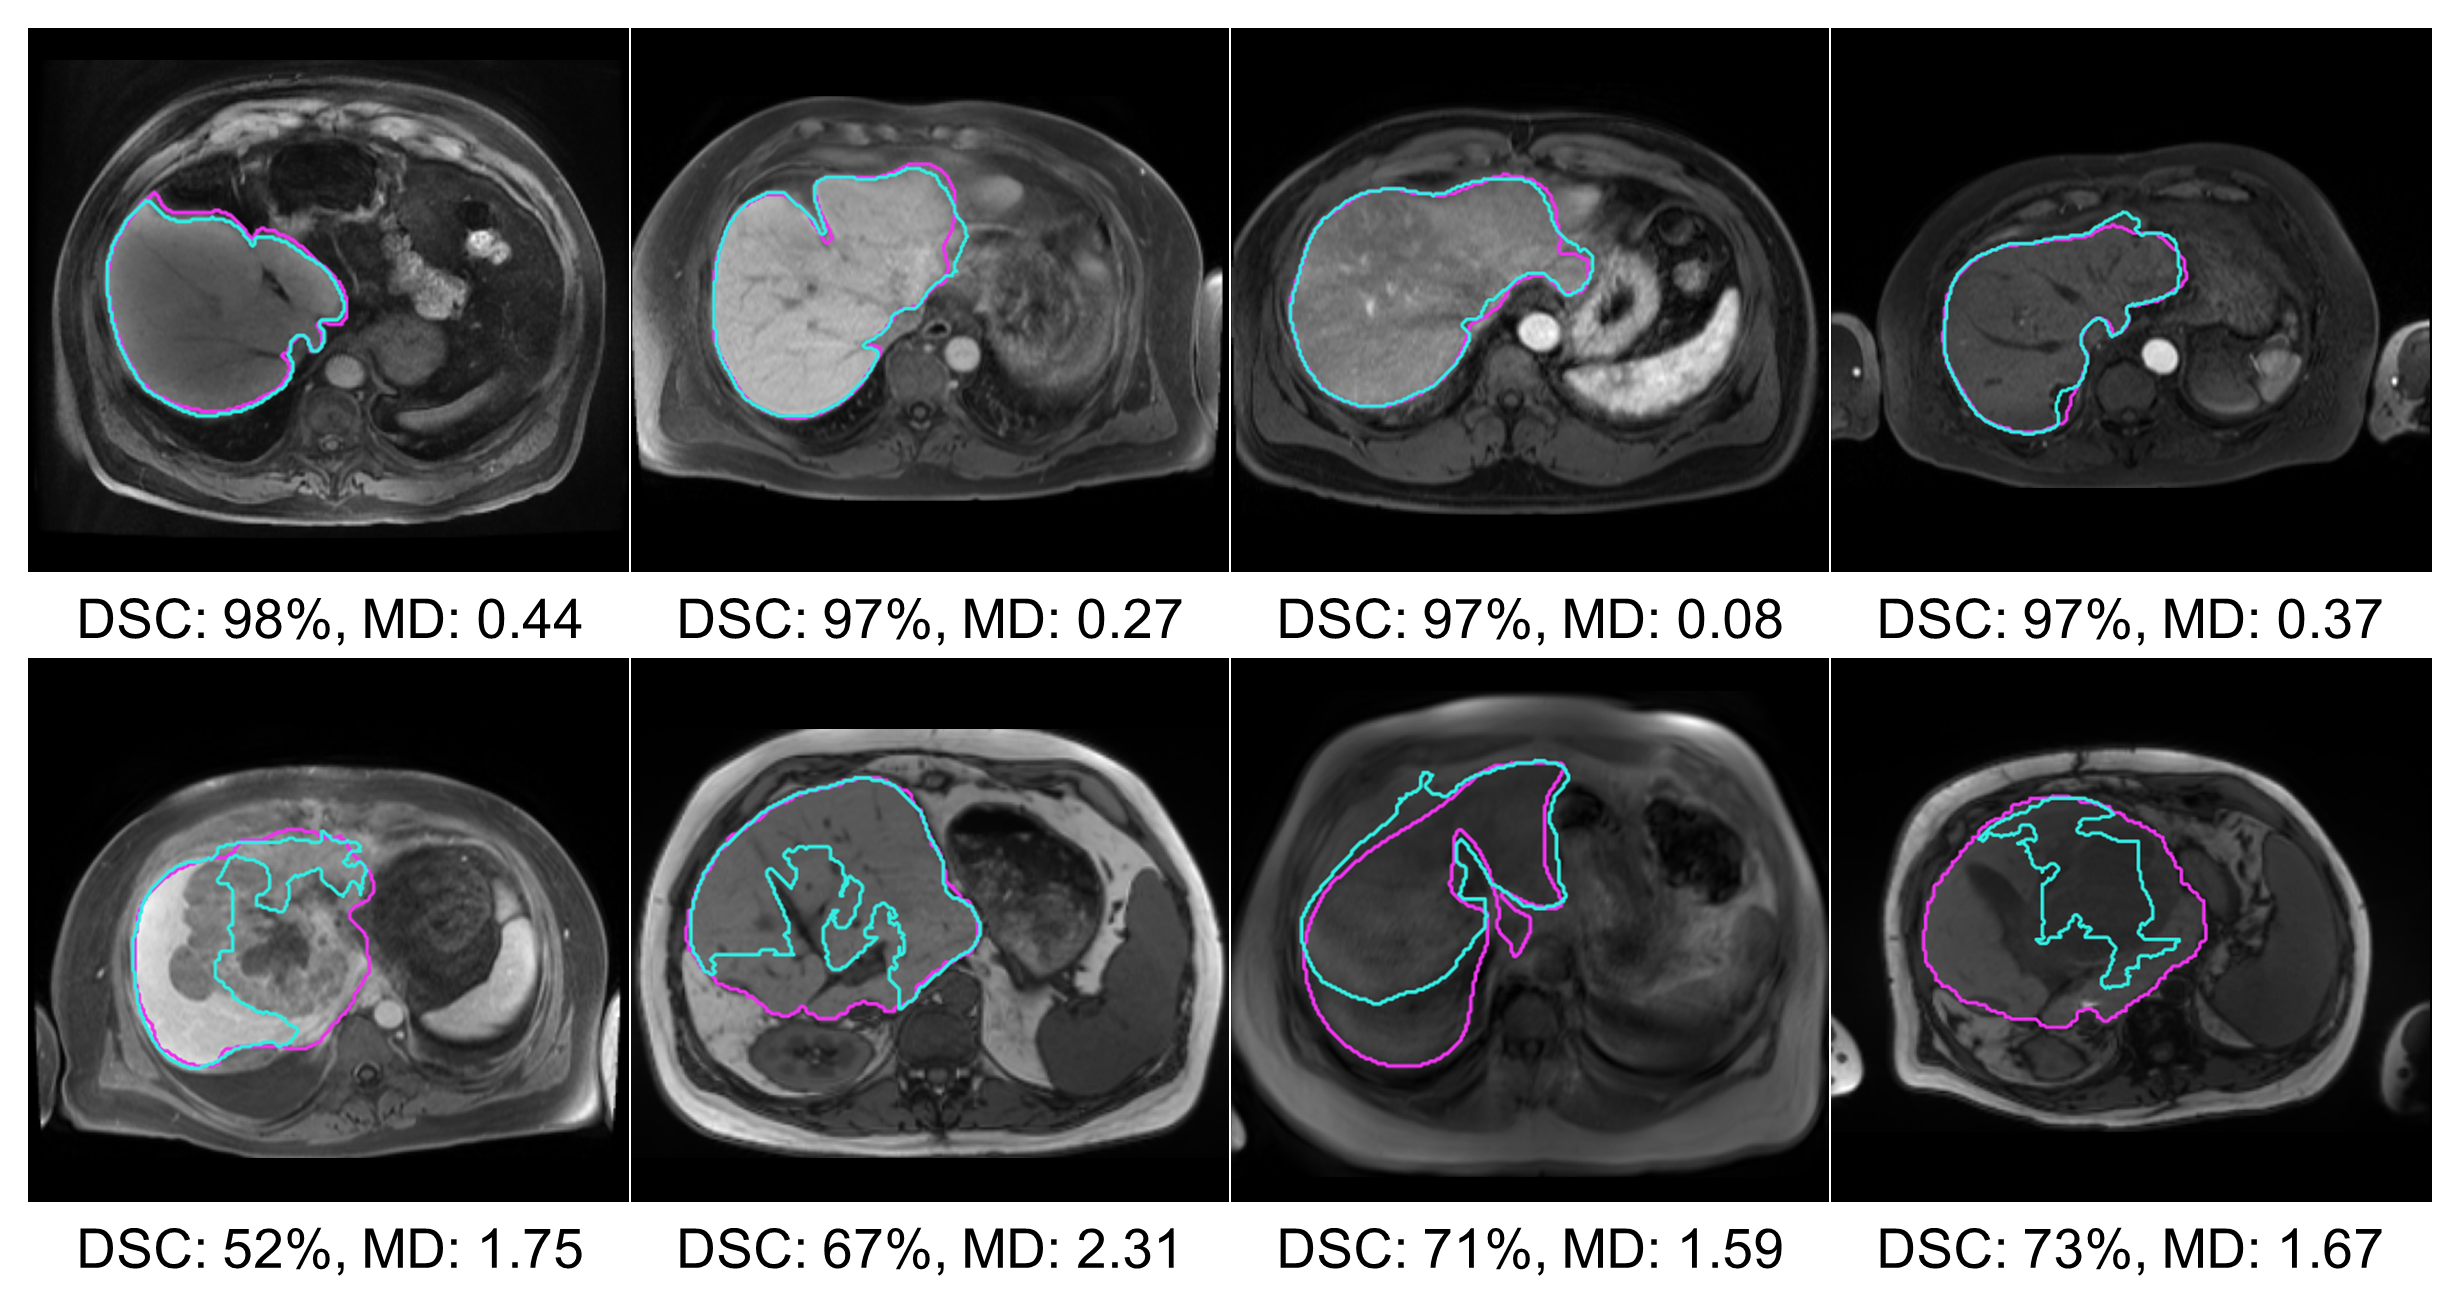

The segmentation performance of the MRI Dropout and MRI Ensemble models improved on that of the MRI UNETR by averaging the predictions (paired t-tests for HD, p=.013𝑝.013p=.013 Dropout, p=.020𝑝.020p=.020 Ensemble; Table 3). Thresholds for OOD detection were set at 95% DSC for all models except the MRI+ UNETR. This model only produced one DSC over 95%, so the threshold was lowered to 80%. 13 images determined to be OOD were shared across the MRI UNETR, MRI Dropout, and MRI Ensemble models. MRI+ UNETR and MRI+ nnU-net performed similarly on MRI+TeTe{}_{\text{Te}}, with MRI+ UNETR achieving a lower HD and MRI+ nnU-net achieving a higher NSD (paired t-tests, p<.001𝑝.001p<.001 all tests). Figure 2 displays visual examples of the segmentation quality of the MRI UNETR.

Refer to caption

Figure 2: Segmentations with high (top) and low (bottom) DSCs along with their corresponding MDs, calculated in conjunction with PCA with two components. Pink is the ground truth segmentation; teal is the MRI UNETR segmentation.

4.2.3 Dimensionality Reduction

Paired with MD, all dimensionality reduction techniques resulted in improvements in the AUROC (t-tests, p=.003𝑝.003p=.003 UMAP/MRI+ UNETR, p<.001𝑝.001p<.001 all other tests; Table 4). On the MRI models, PCA achieved the best performance, outperforming average pooling by 0.14 (±plus-or-minus\pm0.06)% AUROC and 535.11 (±plus-or-minus\pm903.70) seconds. For CT nnU-net, UMAP achieved the best AUROC, outperforming average pooling by 0.09. Figure 2 displays MDs computed on PCA-reduced features, along with the corresponding segmentations. In this figure, higher MDs were associated with poor segmentation performance.